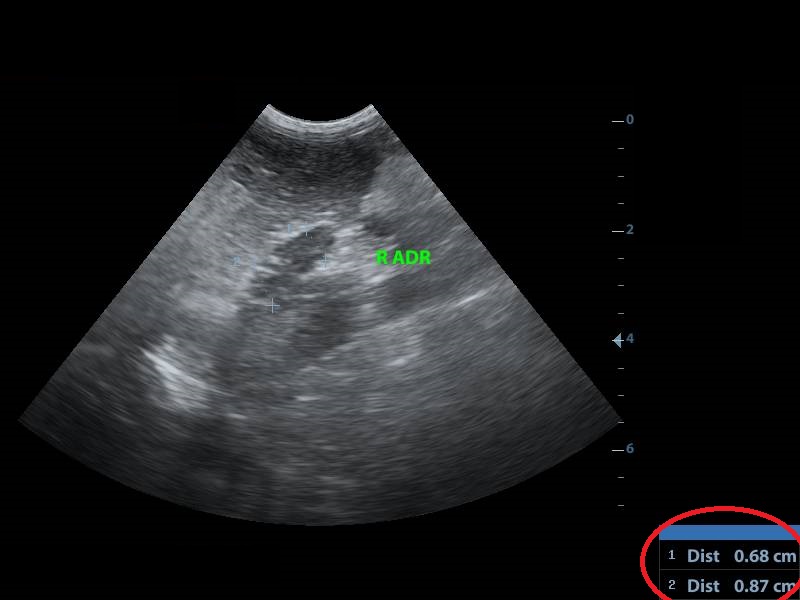

Increased echogenisity of the liver. There was no clear distinction between liver’s parenchyma and the portal’s vein wall.(pic1)

Έντονη αύξηση της ηχογένειας του ηπατικού παρεγχύματος. Δεν ήταν δυνατή η διαφοροποίηση του ηπατικού παρεγχύματος από το τοίχωμα της πυλαίας φλέβας.(pic1)